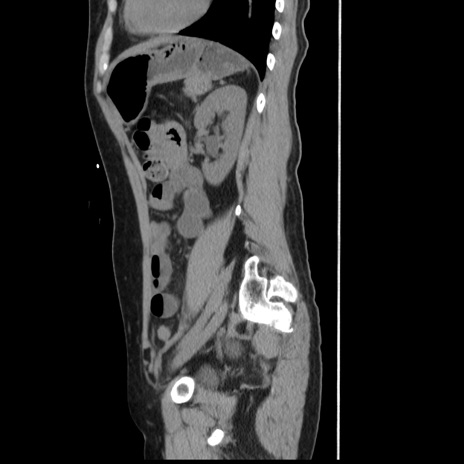

横断像

【症例】 50歳代女性

【主訴】 腹痛

【現病歴】前日生レバーを食べた。今朝に排便あり。 昼前に突然発症の腹痛を生じ、当院救急外来を受診した。

【既往歴】 子宮筋腫にてで子宮全摘後

【身体所見】 意識清明、腹部:平坦、軟、下腹部やや左を中心に圧痛・反跳痛あり、筋性防御あり

【データ】WBC 7800、CRP 0.07